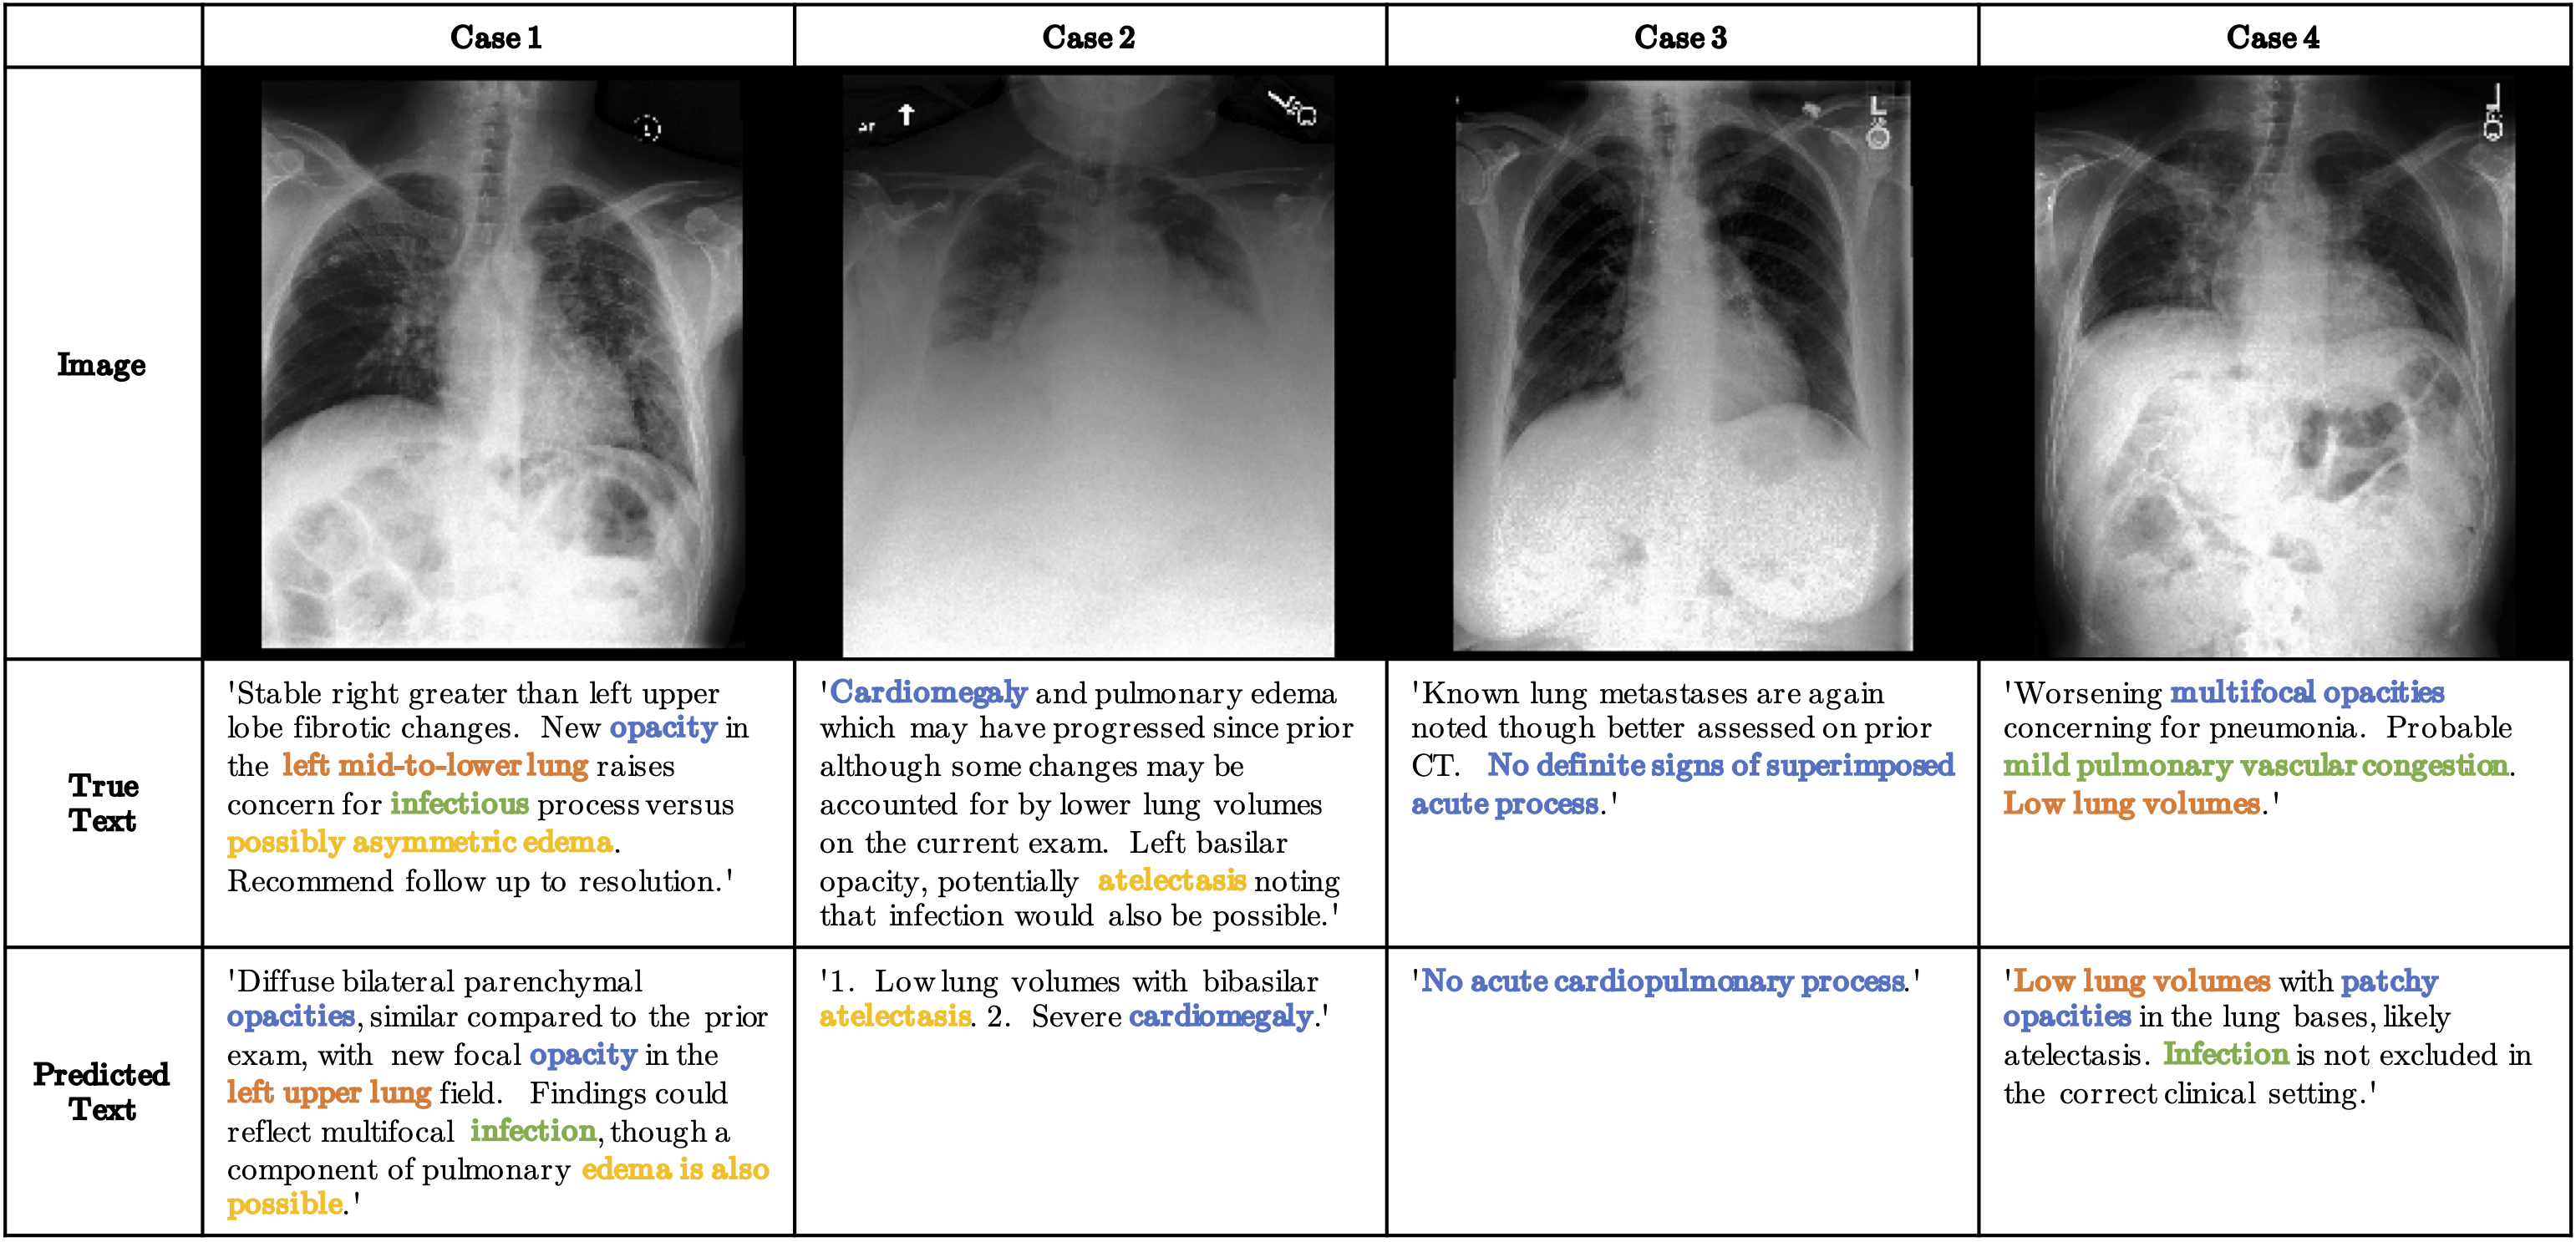

More Examples

More Captioning Examples